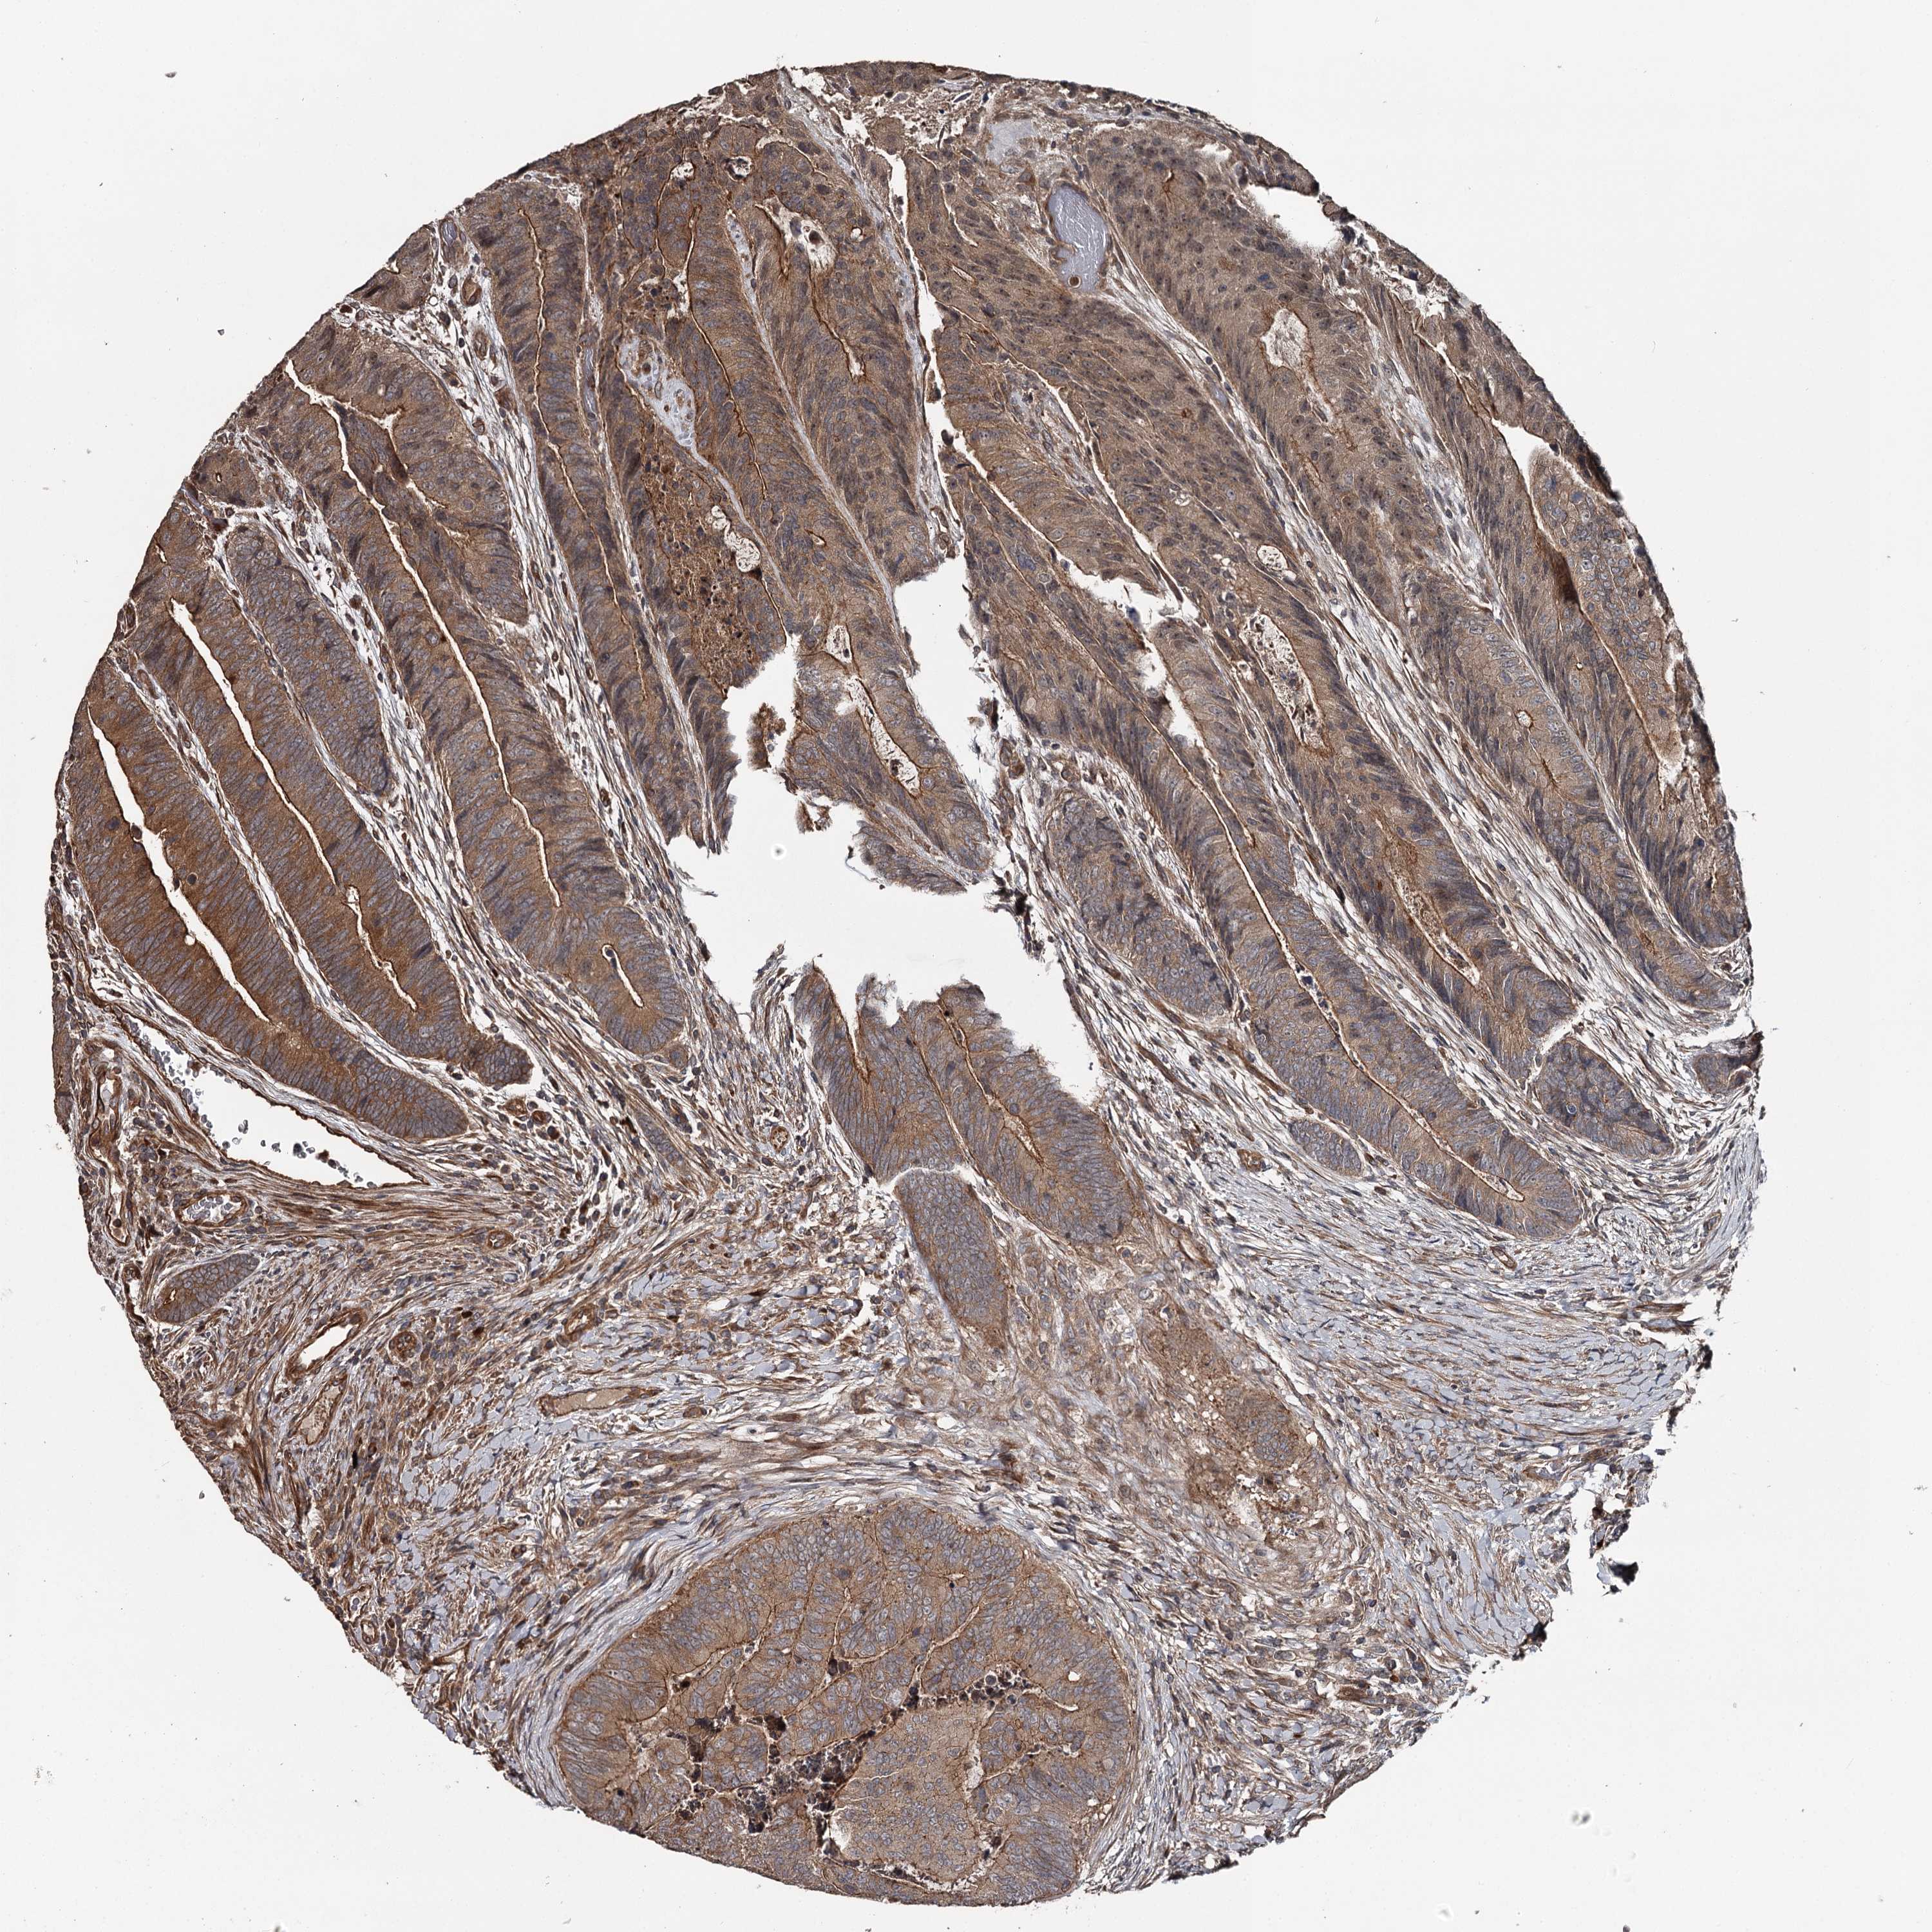

CANCER COLORECTAL CANCER Show tissue menu

Colorectal cancer

Human cancer

Colon adenocarcinoma